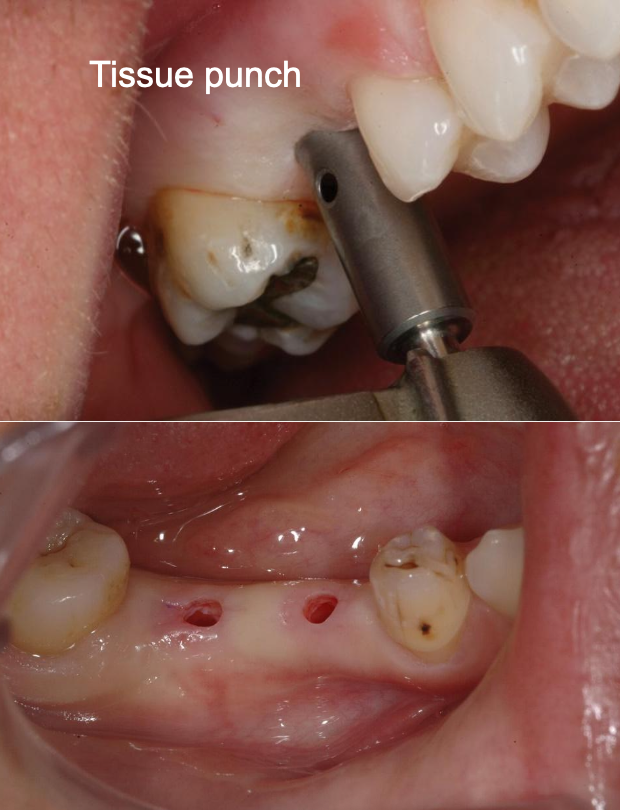

What are you measuring here?

How thick the gum tissue is above the bone

What are the advantages of a flapless surgery?

Minimally invasive surgery

Less trauma to the hard and soft tissues- reduced postoperative symptoms, reduced risks of peri-implant bone loss

Maintained blood supply to the bone: major supra-periosteum vessels, and the vessels of the alveolar bone.

Less bleeding- easier to view the surgical field

Less risk of scarring and gum tissue recession

Reduced surgical time